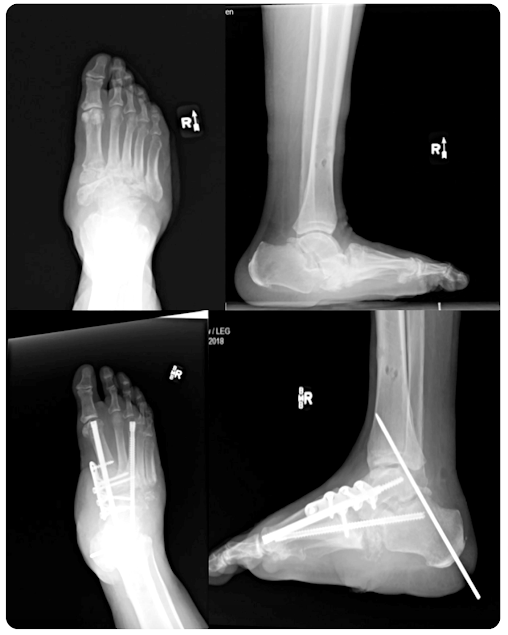

Artropatía de Charcot bilateral tratada con constructos de perno-viga en el contexto de úlceras unilaterales del pie

- Dos pacientes diabéticos tipo 2 presentaron artropatía de Charcot bilateral con colapso del mediopié y presencia de ulceraciones en un lado del pie.

- La extremidad ulcerada de cada paciente se trató quirúrgicamente con pernos de fusión, vigas y placas en el contexto de una ulceración abierta.

- Las extremidades bilaterales se trataron quirúrgicamente y se procedió a la consolidación ósea y la cicatrización de la herida.